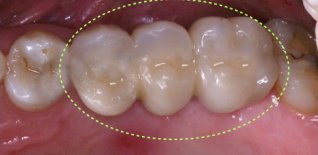

Grande rialzo del seno mascellare

Perdita di elementi dentari postero-superiori di destra, con assenza di osso per poter posizionare impianti osteo-integrati.

Si rigenera l'osso necessario attraverso l'intervento di GRANDE RIALZO DEL SENO MASCELLARE.

A rigenerazione ossea stabilizzata si procede all'inserzione degli impianti e alle fasi protesiche definitive.